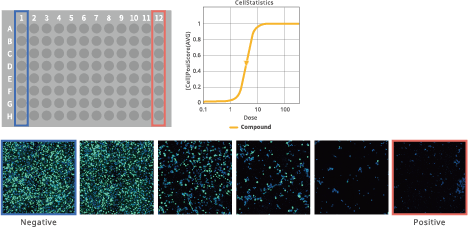

EC50/IC50 calculation (deep image response)

Image Credit: Yokogawa Life Science

Using whole images, this function allows for the thorough quantification of complicated phenotypes. Simple process of entering compound concentration data and choosing positive and negative wells. There is no need for any process to segment cells.

EC50/IC50 calculation (deep image response)

Image Credit: Yokogawa Life Science

This feature makes it possible to use whole images to measure complicated phenotypes thoroughly. Choosing positive and negative wells and entering information regarding compound concentration is simple. Segmentation of cells does not require any methodology.